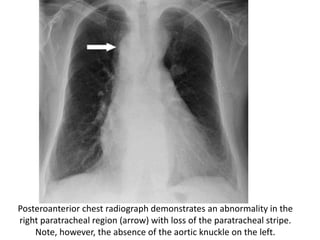

Posteroanterior chest radiograph demonstrates an abnormality in the

right paratracheal region (arrow) with loss of the paratracheal stripe.

Note, however, the absence of the aortic knuckle on the left.